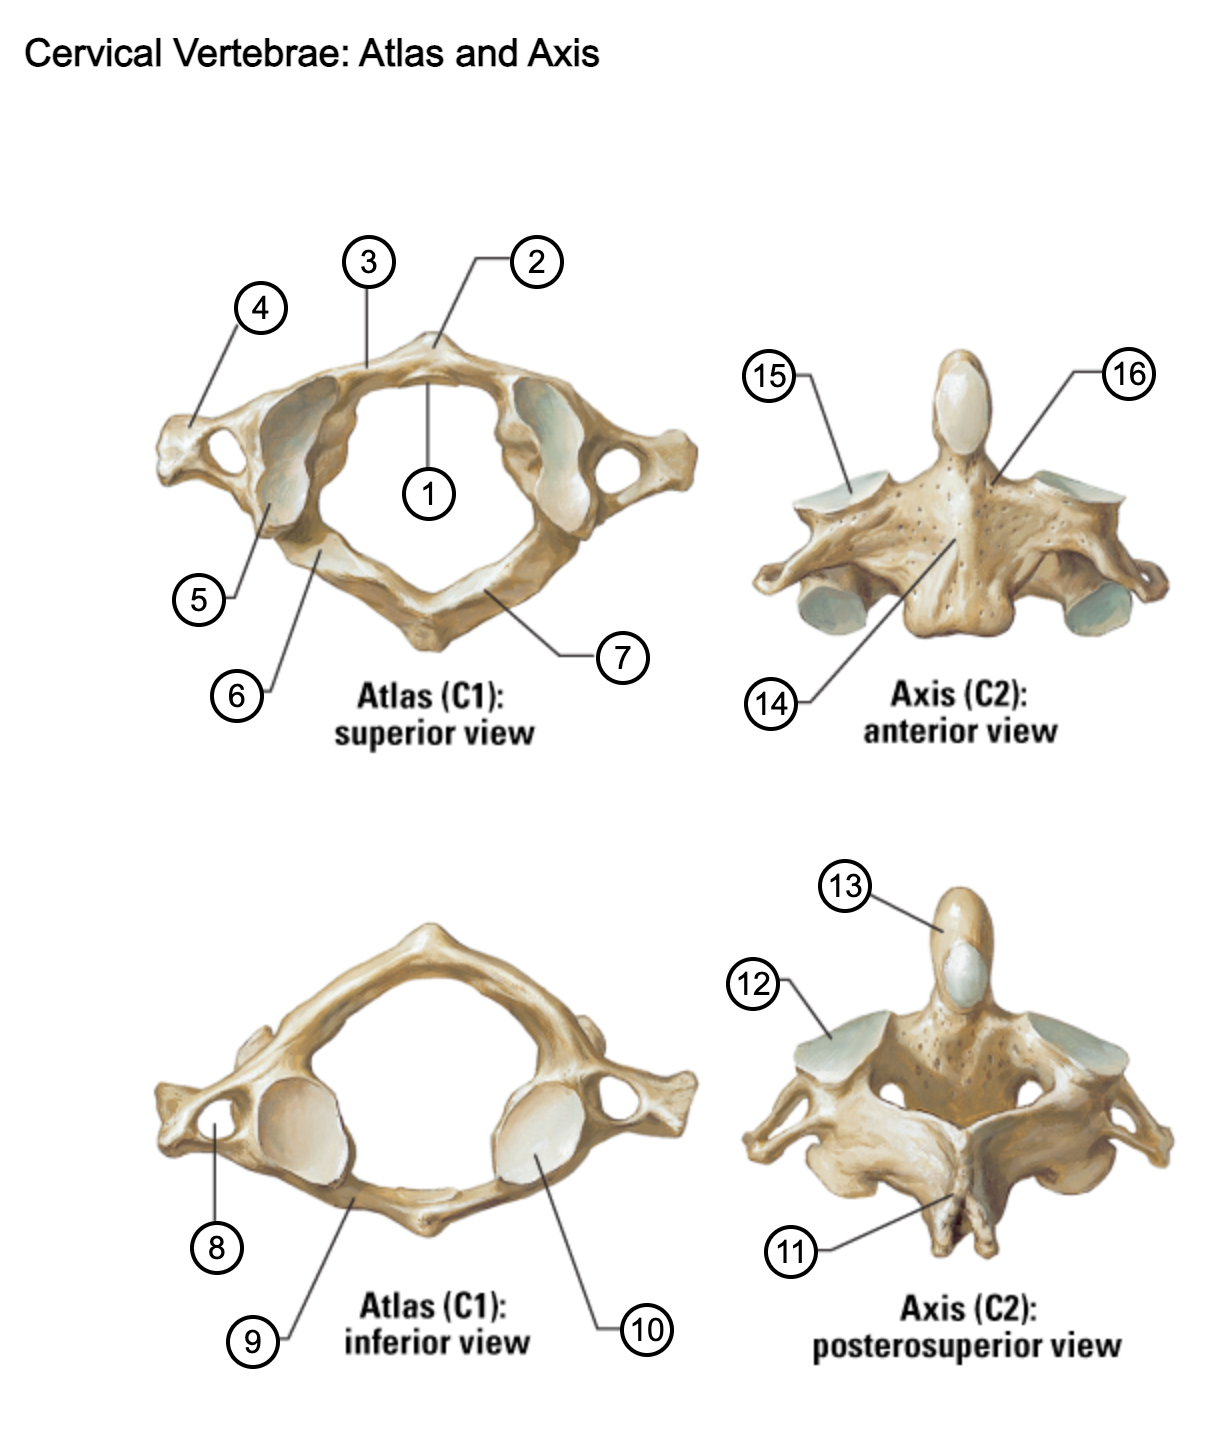

1

facet for dens

2

anterior tubercle

3

anterior arch

4

transverse process

5

superior articular surface of atlas

6

groove for vertebral artery

7

posterior arch

8

transverse foramen

9

anterior arch

10

inferior articular surface of atlas

11

spinous process

12

superior articular facet

13

dens of axis

14

body of axis

15

superior articular facet for atlas

16

pedicle of vertebral arch